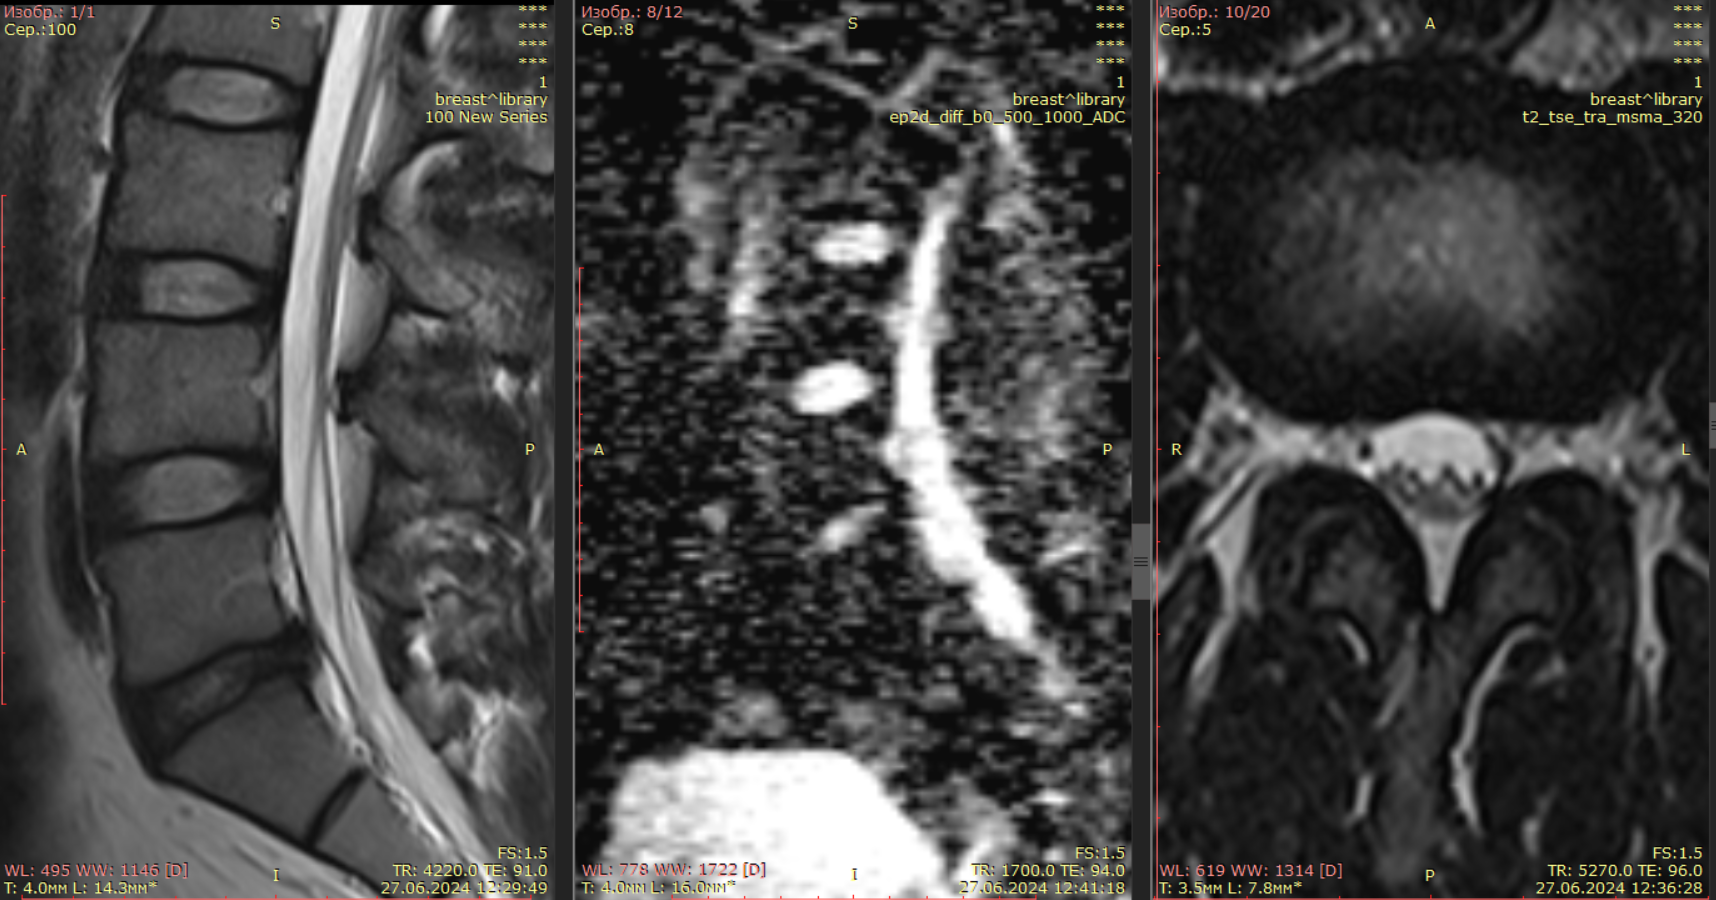

Проведен анализ магнитно-резонансных томограмм дегенерированных так и не дегенерированных дисков (рис. 1).

а                                        б                                             в

Рис. 1. МРТ изображение поясничного отдела позвоночника с дегенерированными дисками и не дегенерированным диском: а) Т2 взвешенное изображение c указанными позвоночно-двигательными сегментами (ПДС); б) диффузно-взвешенное изображение с измеренными показателями ИКД дисков и ликвора в сагиттальной плоскости; в) аксиальный срез исследуемой зоны.

Fig. 1. MRI image of the lumbar spine with degenerated discs and a non-degenerated disc: a) T2-weighted image with the spinal motion segments indicated; b) diffusely weighted image with measured values of ICD discs and cerebrospinal fluid in the sagittal plane; c) axial section of the studied area.

Коэффициент Х рассчитывался на уровне ПДС LIII/LIV, LIV/LV, LV/SI (таблица 1).

Межпозвонковые диски LIII/LIV и LIV/LV на Т2 взвешенном изображении имеют четкое разделение фиброзного кольца и пульпозного ядра, гиперинтенсивный сигнал, нормальную высоту межпозвонкового диска, гомогенную структуру.

Однако, после вычисления коэффициента Х по предлагаемой формуле установлено, что диск на уровне ПДС LIII/LIV имеет меньшее значение, чем диск LIV/LV. Проанализированное МРТ исследование показало, что межпозвонковый диск LIII/LIV имеет менее гомогенную структуру и поэтому был отнесен к I степени дегенерации по Pfirrmann CW. Хотя диски LIII/LIV и LIV/LV визуально не значительно отличаются друг от друга, но при этом коэффициенты Х этих дисков имеют существенную разницу по их величине.

Установлено, что чем ниже значение коэффициента Х, тем больше выражены дегенеративные изменения в диске.